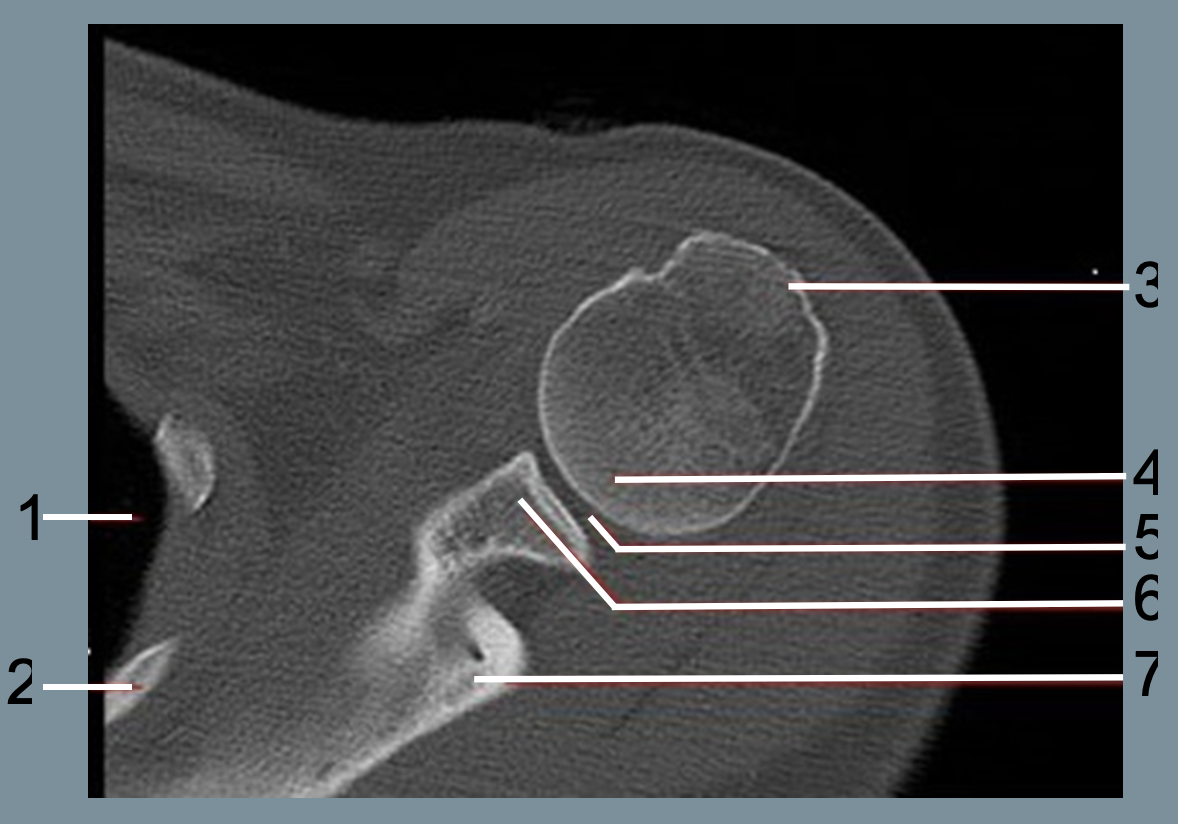

1

lung

2

rib

3

greater tubercle

4

humeral head

5

glenohumeral joint

6

glenoid process

7

scapular spine